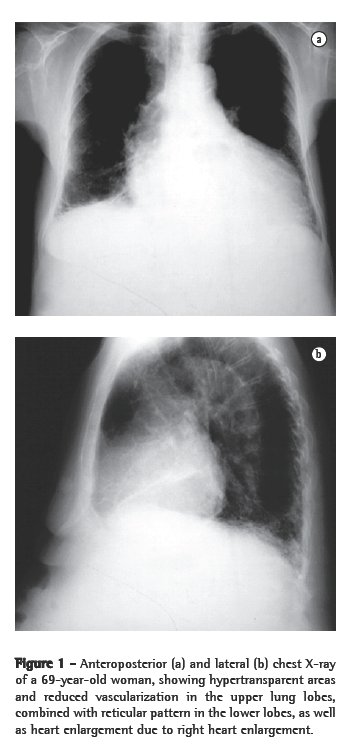

On chest X-rays and HRCT scans, all patients presented findings consistent with emphysema and IPF (Figures 1 and 2). Radiotransparent areas were seen in the upper lobes on X-rays in all cases. Reticular opacities were present in the lung bases in 6 cases. All but 2 patients presented honeycombing. Areas of attenuation appeared as ground-glass opacities in 4 cases. Traction bronchiectasis was described in 3 of the 11 cases. Of the total number of patients in this study, 5 presented a PaO2 < 70 mmHg at rest, which was determined by arterial blood gas analysis on room air. The mean pH, arterial carbon dioxide tension, bicarbonate, PaO2, and arterial oxygen saturation were 7.44 ± 0.03, 32.8 ± 6.7 mmHg, 21.5 ± 3.6 mmol/L, 68.9 ± 11.9 mmHg, and 94.2% ± 3.3%, respectively. None of the patients presented hypercapnia.